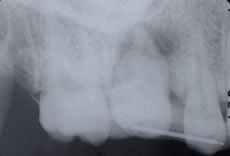

![]() |

移植手術後のレントゲン |